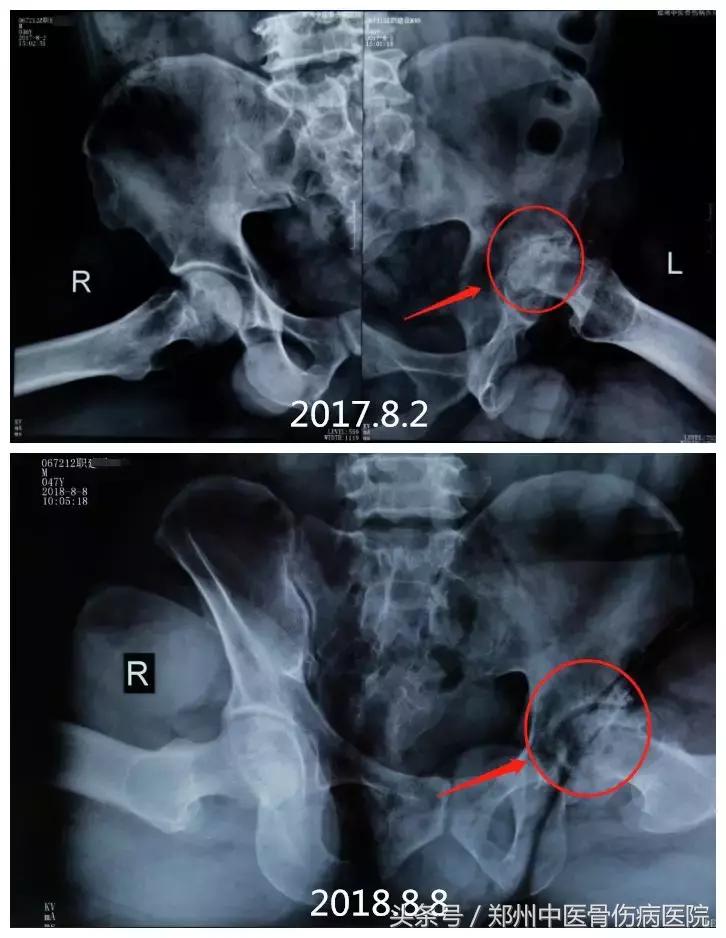

下图为患者职某片子对比图:

2017年8月2日治疗前,骨盆倾斜严重,导致双下肢不等长,走路严重跛行;2018年8月8日,经治疗后,已基本恢复正常,大大提高了生活质量。

2018年8月8日片子显示,左侧股骨头骨小梁清晰,骨密度均匀,出现间隙。